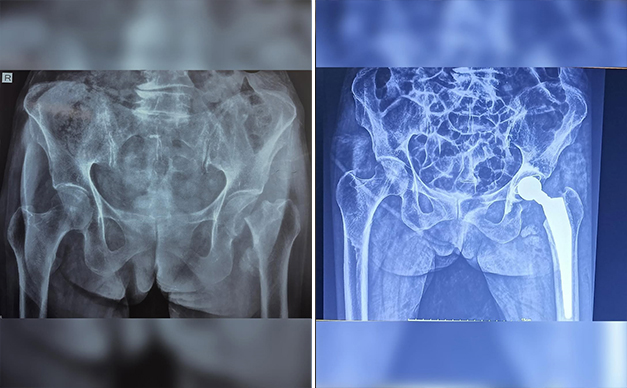

After almost 2 months of sustaining a fracture in her hip, she faced pain, immobility, and uncertainty. But with determination, the support of her family, and modern medicine, she underwent a total hip replacement — a procedure many wouldn’t imagine at this age.

Today, she’s walking again, smiling, and embracing life with the strength that only a century of experiences can build. Her journey reminds us that it’s never too late to reclaim our joy, resilience, and willpower. Every step she takes is a testament to the human spirit’s ability to overcome, to heal, and to inspire.